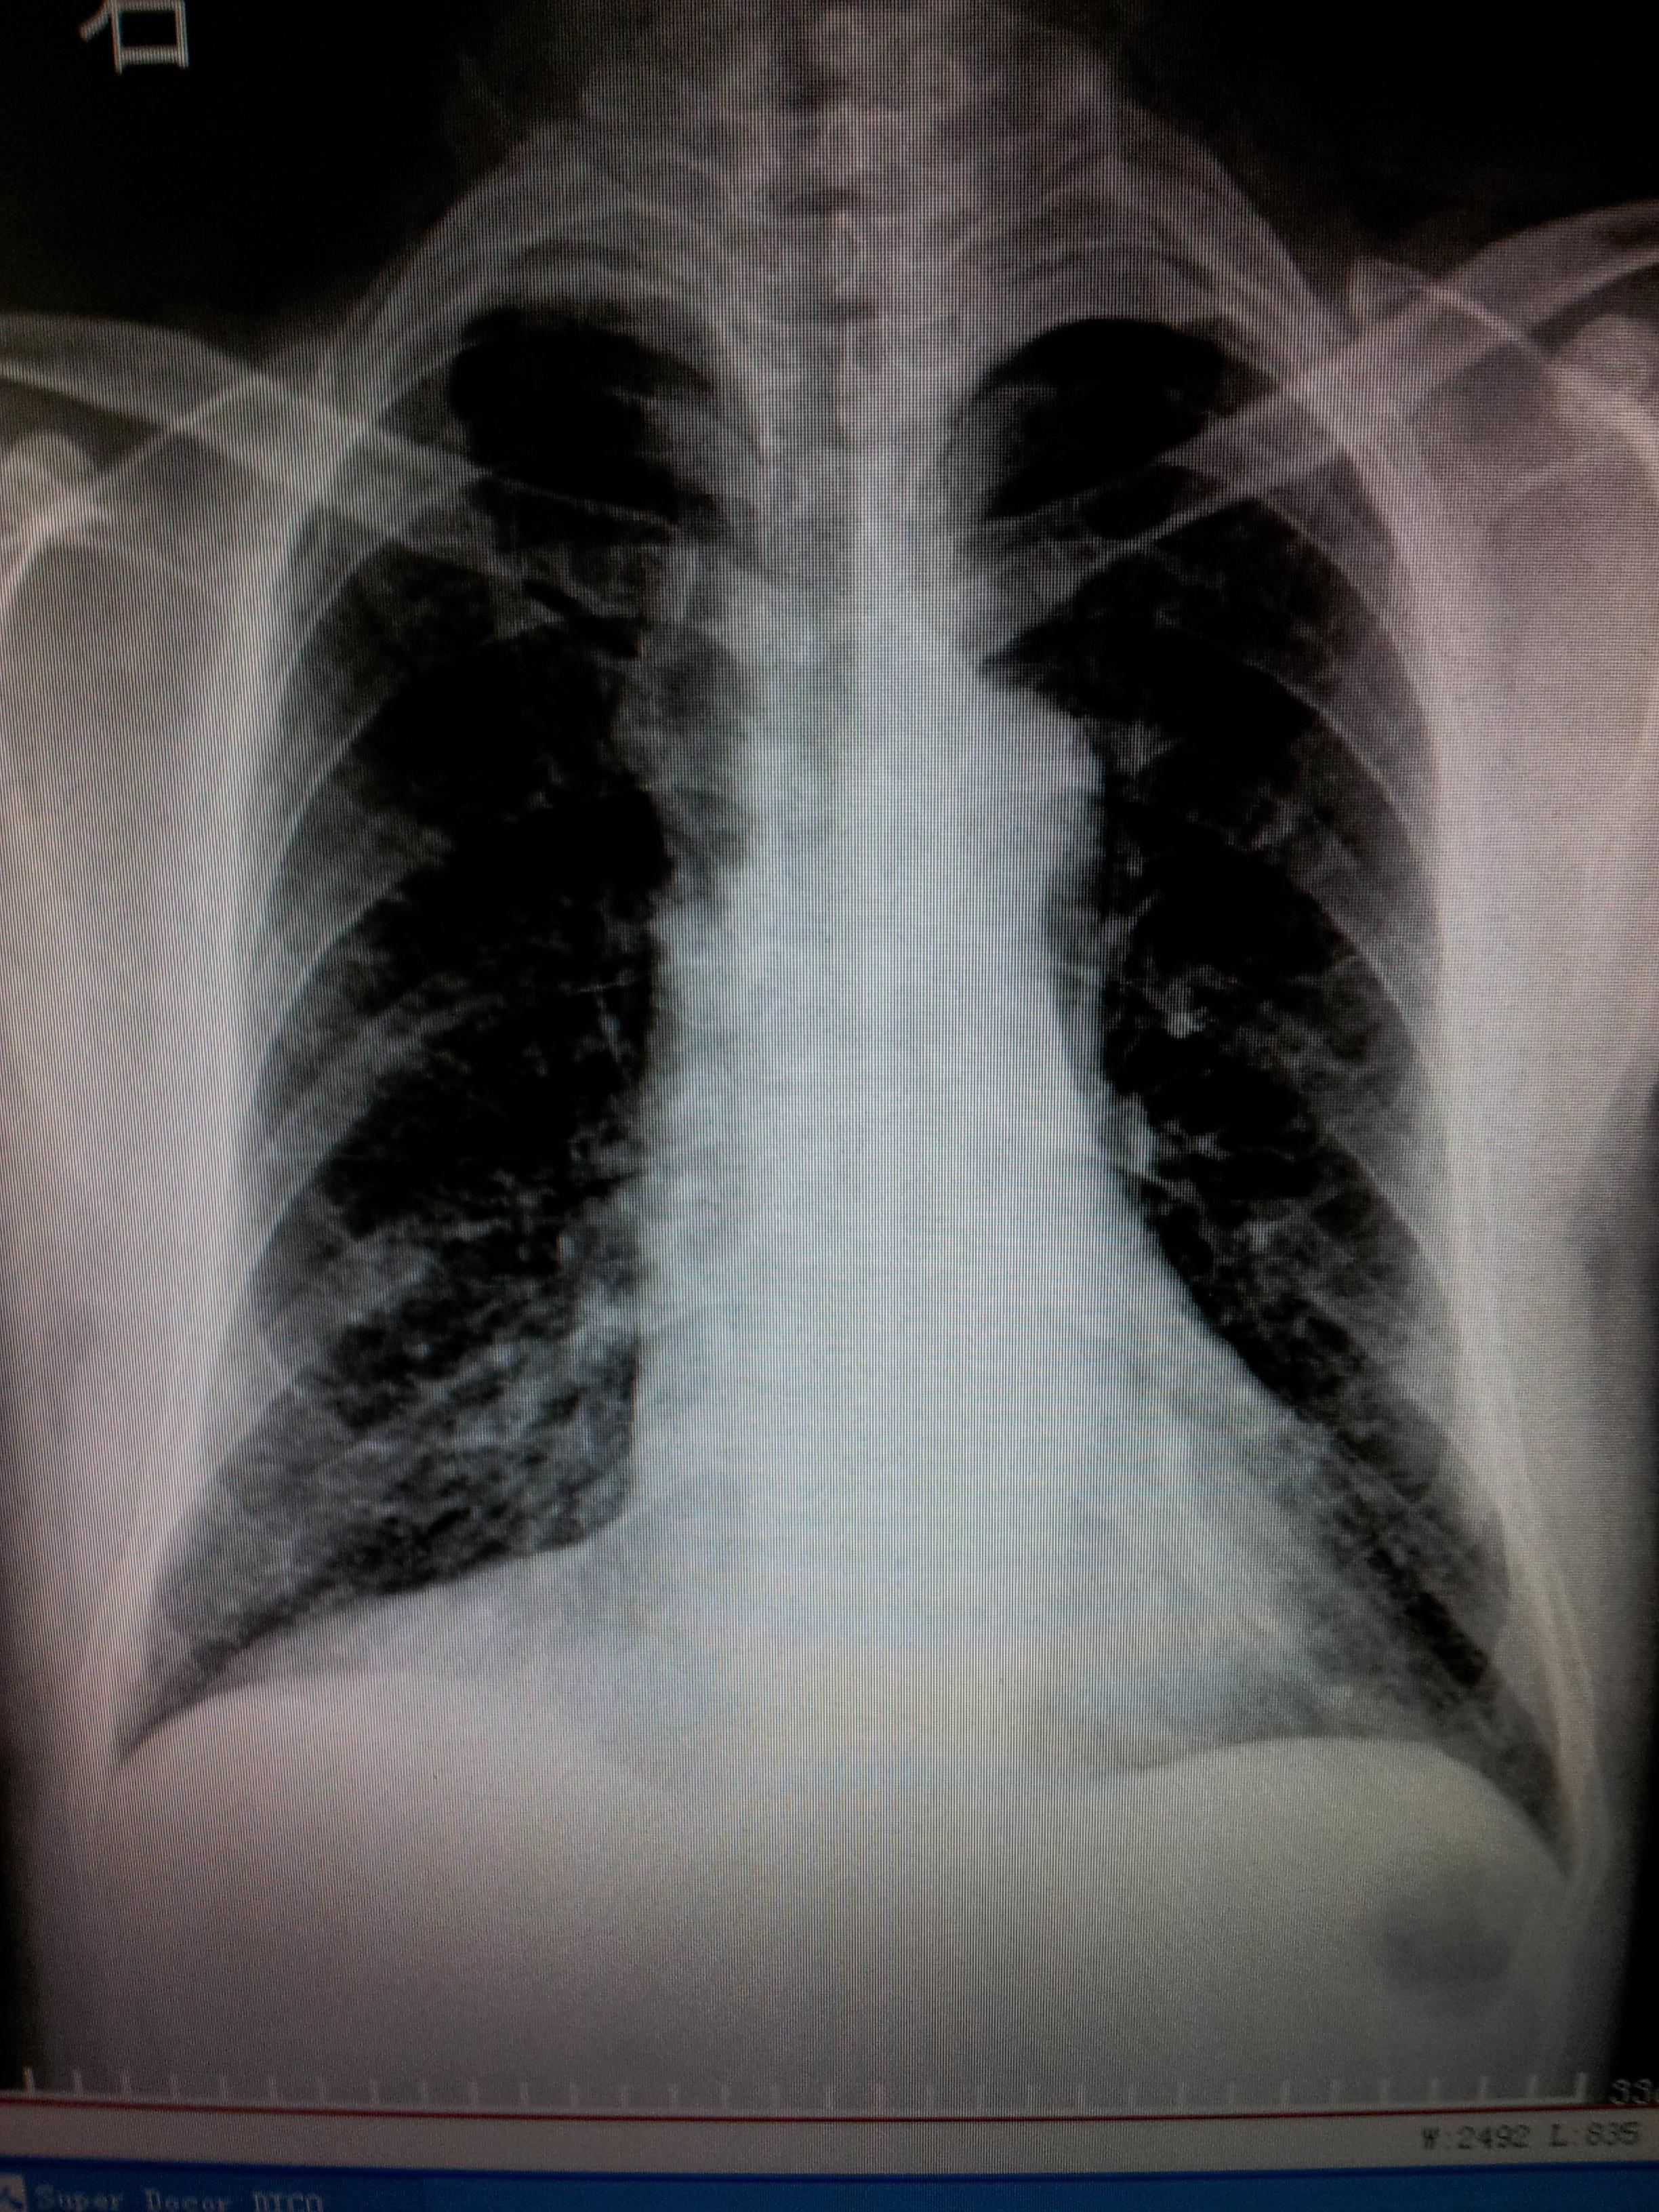

男,52岁,右心膈角是什么?

超越心包位置太多了,明显靠外了。肯定不是心包脂肪垫。如果的一个侧位就好了。提出一个可能“波浪膈”。欢迎质疑。

三角形的,结合透视看看,肺部张不能除外的。

同意楼上,心包脂肪垫。